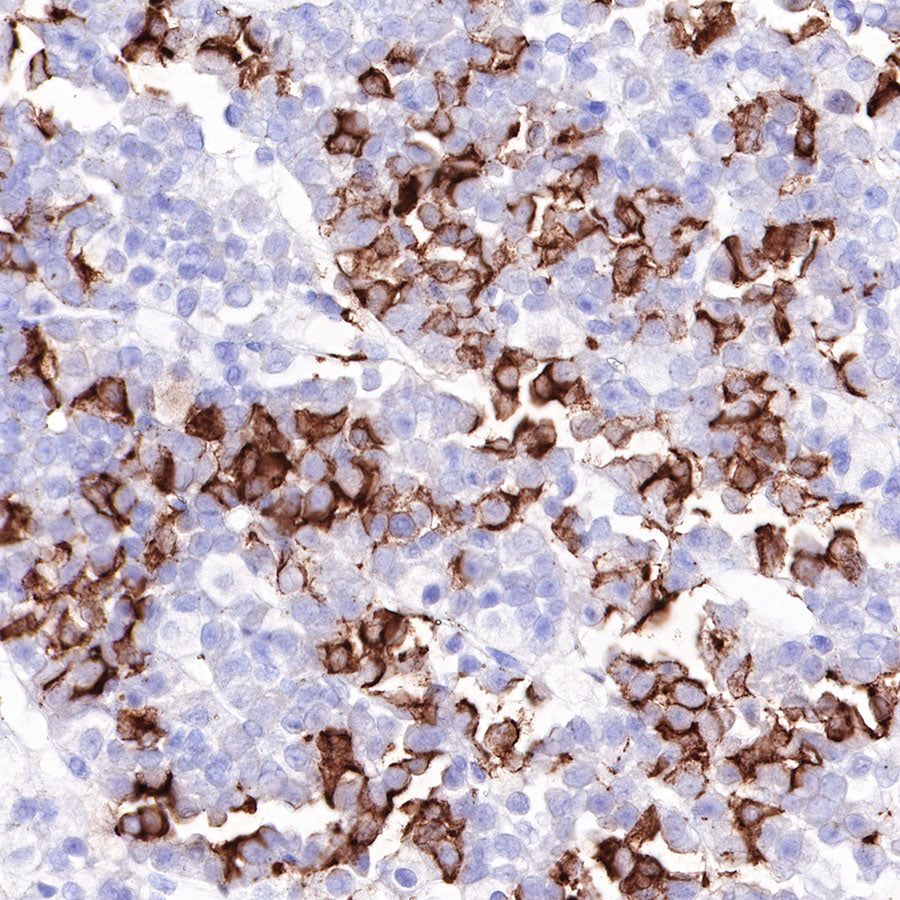

IHC shows positive staining in paraffin-embedded human pituitary. Anti-ACTH antibody was used at 1/2000 dilution, followed by a HRP Polymer for Mouse & Rabbit IgG (ready to use). Counterstained with hematoxylin. Heat mediated antigen retrieval with Tris/EDTA buffer pH9.0 was performed before commencing with IHC staining protocol.